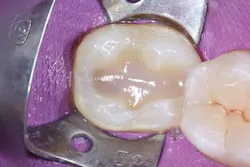

The selective etching technique was chosen, and 37% phosphoric acid (Total Etch, Ivoclar Vivadent) was applied for 30 seconds. The tooth was irrigated with water spray and air-dried (figure 2). Next, a universal bonding agent (Adhese Universal, Ivoclar Vivadent) was scrubbed on the cavity surface until an immobile layer was achieved (figure 3). The excess solvent was removed with an air stream for 20 seconds, and the adhesive was light cured for 10 seconds with an LED light (Bluephase Style, Ivoclar Vivadent) 1 mm away from the cavity.